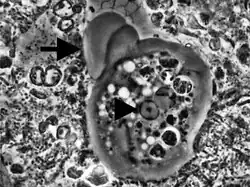

Não possui o estágio de cisto, somente de trofozoíta. Mede cerca de 10 a 35 micrômetros de diâmetro. Possui ectoplasma claro, endoplasma granuloso, vacúolos alimentares contendo restos celulares, bactérias e hemácias. O núcleo é aproximadamente esférico, membrana nuclear com grânulos de cromatina situados muito próximos uns dos outros, cariossomo central. Movimenta-se através de pseudópodes.